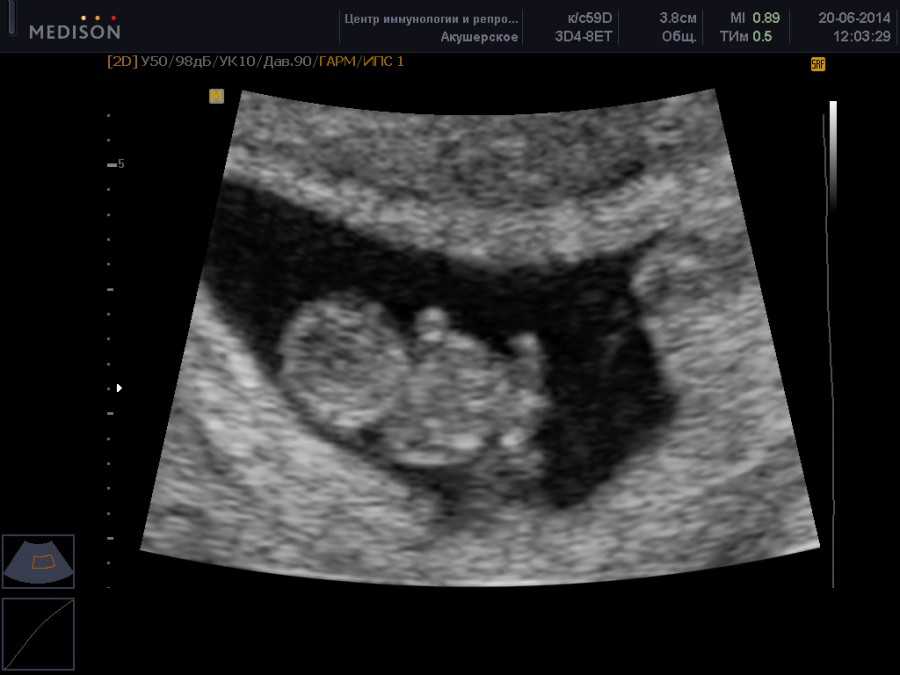

Также показано ультразвуковое исследование плода. Процедура УЗИ позволяет определить срок беременности, толщину плаценты, а также общее состояние яичников и пуповины.

УЗИ на 9-ой неделе беременности

На УЗИ плода на 9 неделе определяется толщина плаценты и общее состояние пуповины. При помощи допплера, будущая мама может отметить частоту сердечных сокращений малыша. Хотя многие внутренние органы уже достаточно развиты, это не всегда можно увидеть на УЗИ на 9 неделе.

Внутренние органы крохи еще могут выступать в виде пупочной грыжи, но нет повода для беспокойства, ведь это совершенно нормальное явление.

На УЗИ на данном сроке обязательным является общая оценка состояния яичников.

УЗИ на сроке 9 недель